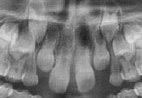

Este diastema, presente por volta dos 8 aos 11 anos, é esperado e geralmente fecha completamente após a erupção dos caninos permanentes superiores. A tentativa de fechá-lo ortodônticamente geralmente é desastrosa, pois, nesta fase da dentição mista, os caninos permanentes ainda não erupcionados estão em íntimo contato com as raízes dos incisivos laterais permanentes (como observado na radiografia). Assim, o movimento de fechamento do diastema joga as raízes dos incisivos centrais em direção aos laterais e, as raízes dos laterais, em direção aos caninos. E os caninos podem ficar sem espaço para erupção. A partir de então teremos um problemas ortodôntico verdadeiro: impacção dos caninos permanentes (eles ficam retidos dentro do osso, não erupcionam).